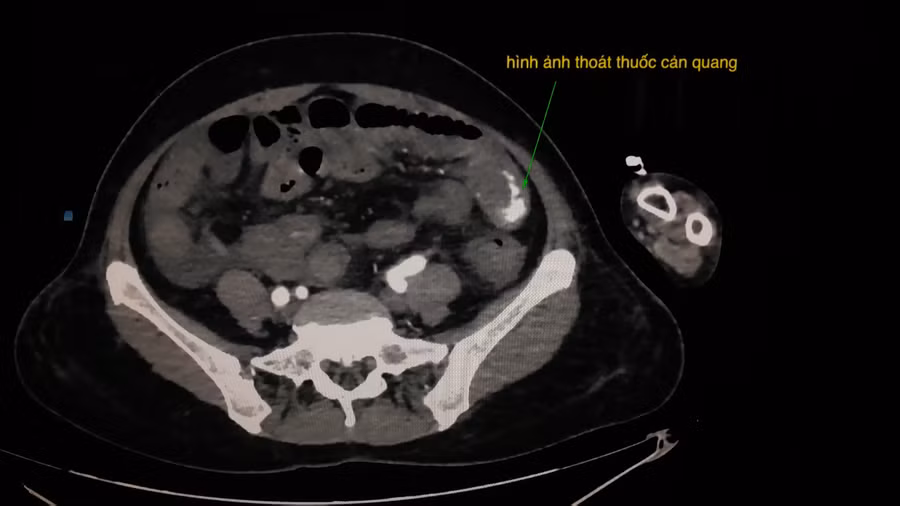

![]() |

| Hình ảnh chụp cắt lớp vi tính bụng của bệnh nhân L. có cản quang. |